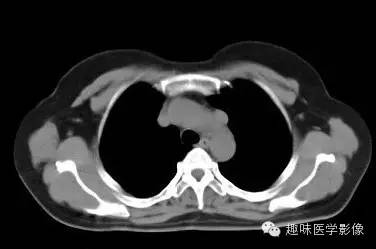

两肺未见明显异常。纵隔左侧见血管影,经主动脉弓与左肺肺门之前向下走行,汇入冠状静脉窦。

永存左上腔静脉